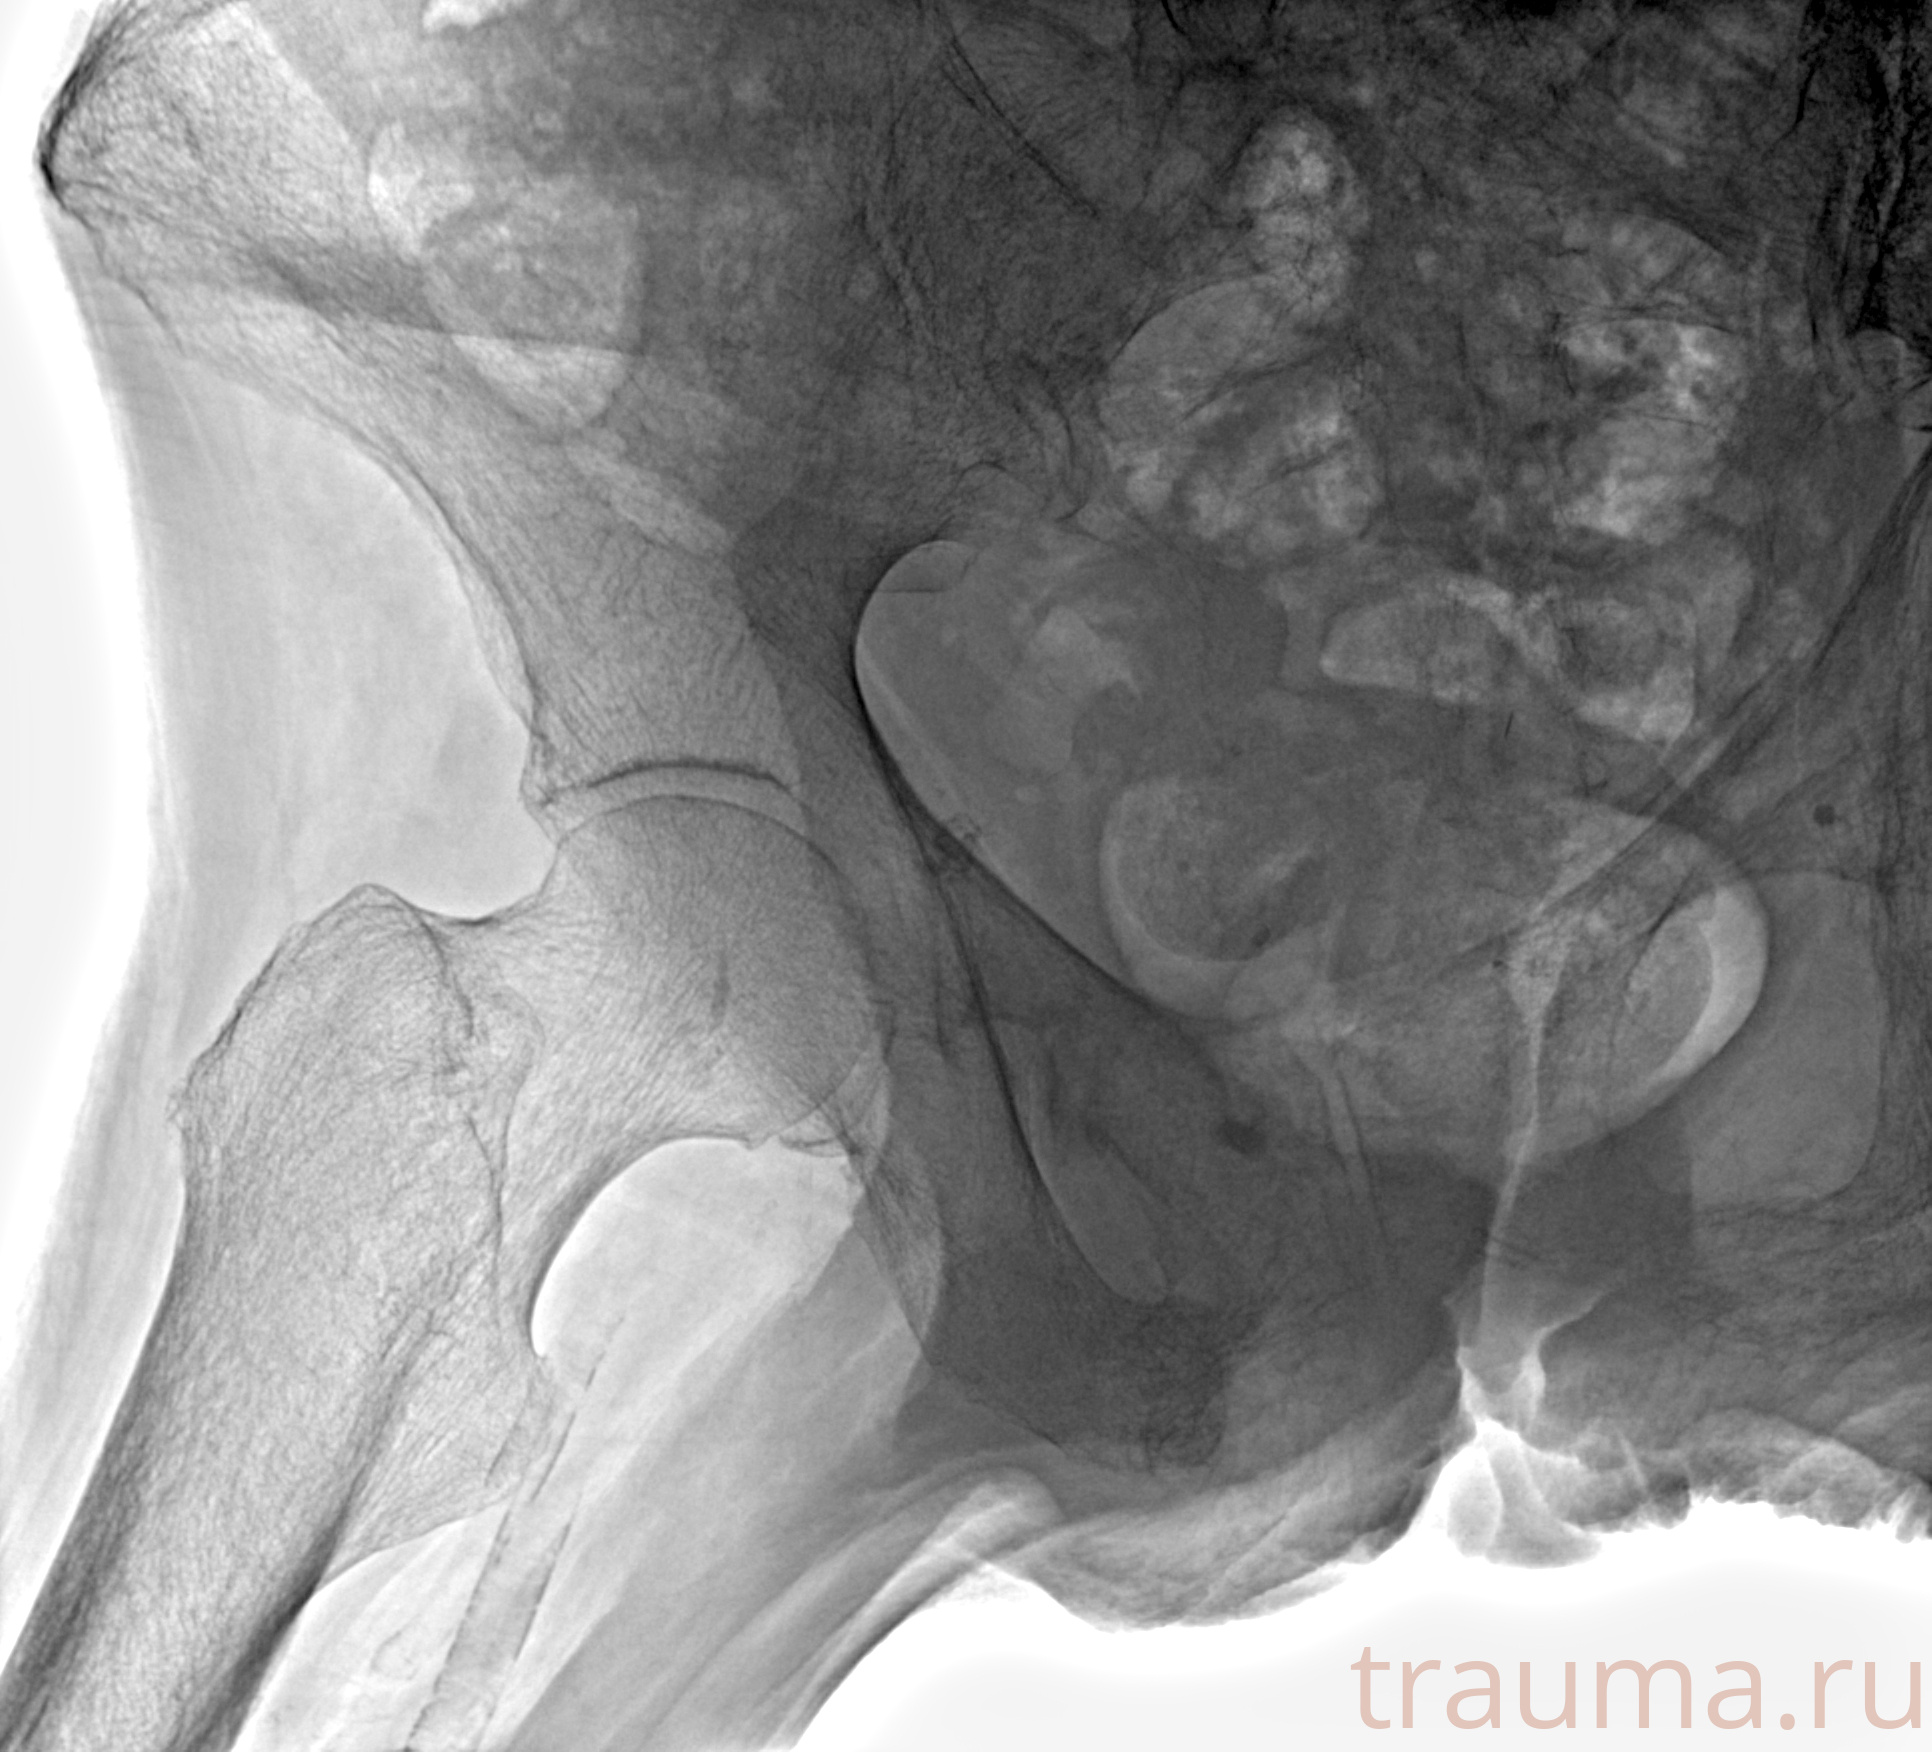

Рентген на дому: по вашему адресу приезжает врач-рентгенолог, травматолог-ортопед с мобильным рентгеновским аппаратом, проводит диагностику травмы или заболевания, делает необходимые рентгенограммы, дает рекомендации по дальнейшему лечению. Получить качественные снимки в домашних условиях возможно благодаря уникальной методике, разработанной МосРентген Центром для института  Склифосовского